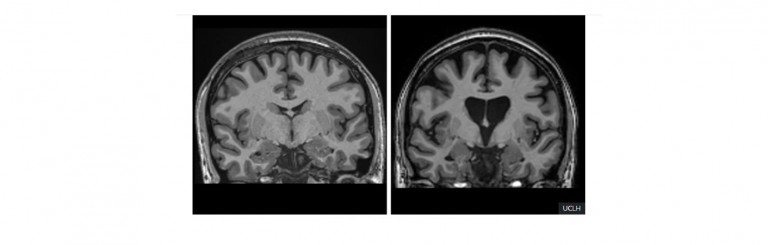

(Left image) Healthy brain tissue. (Right image) Huntington's ruinous impact on brain tissue. Image credit: University College London. Article by Graham...